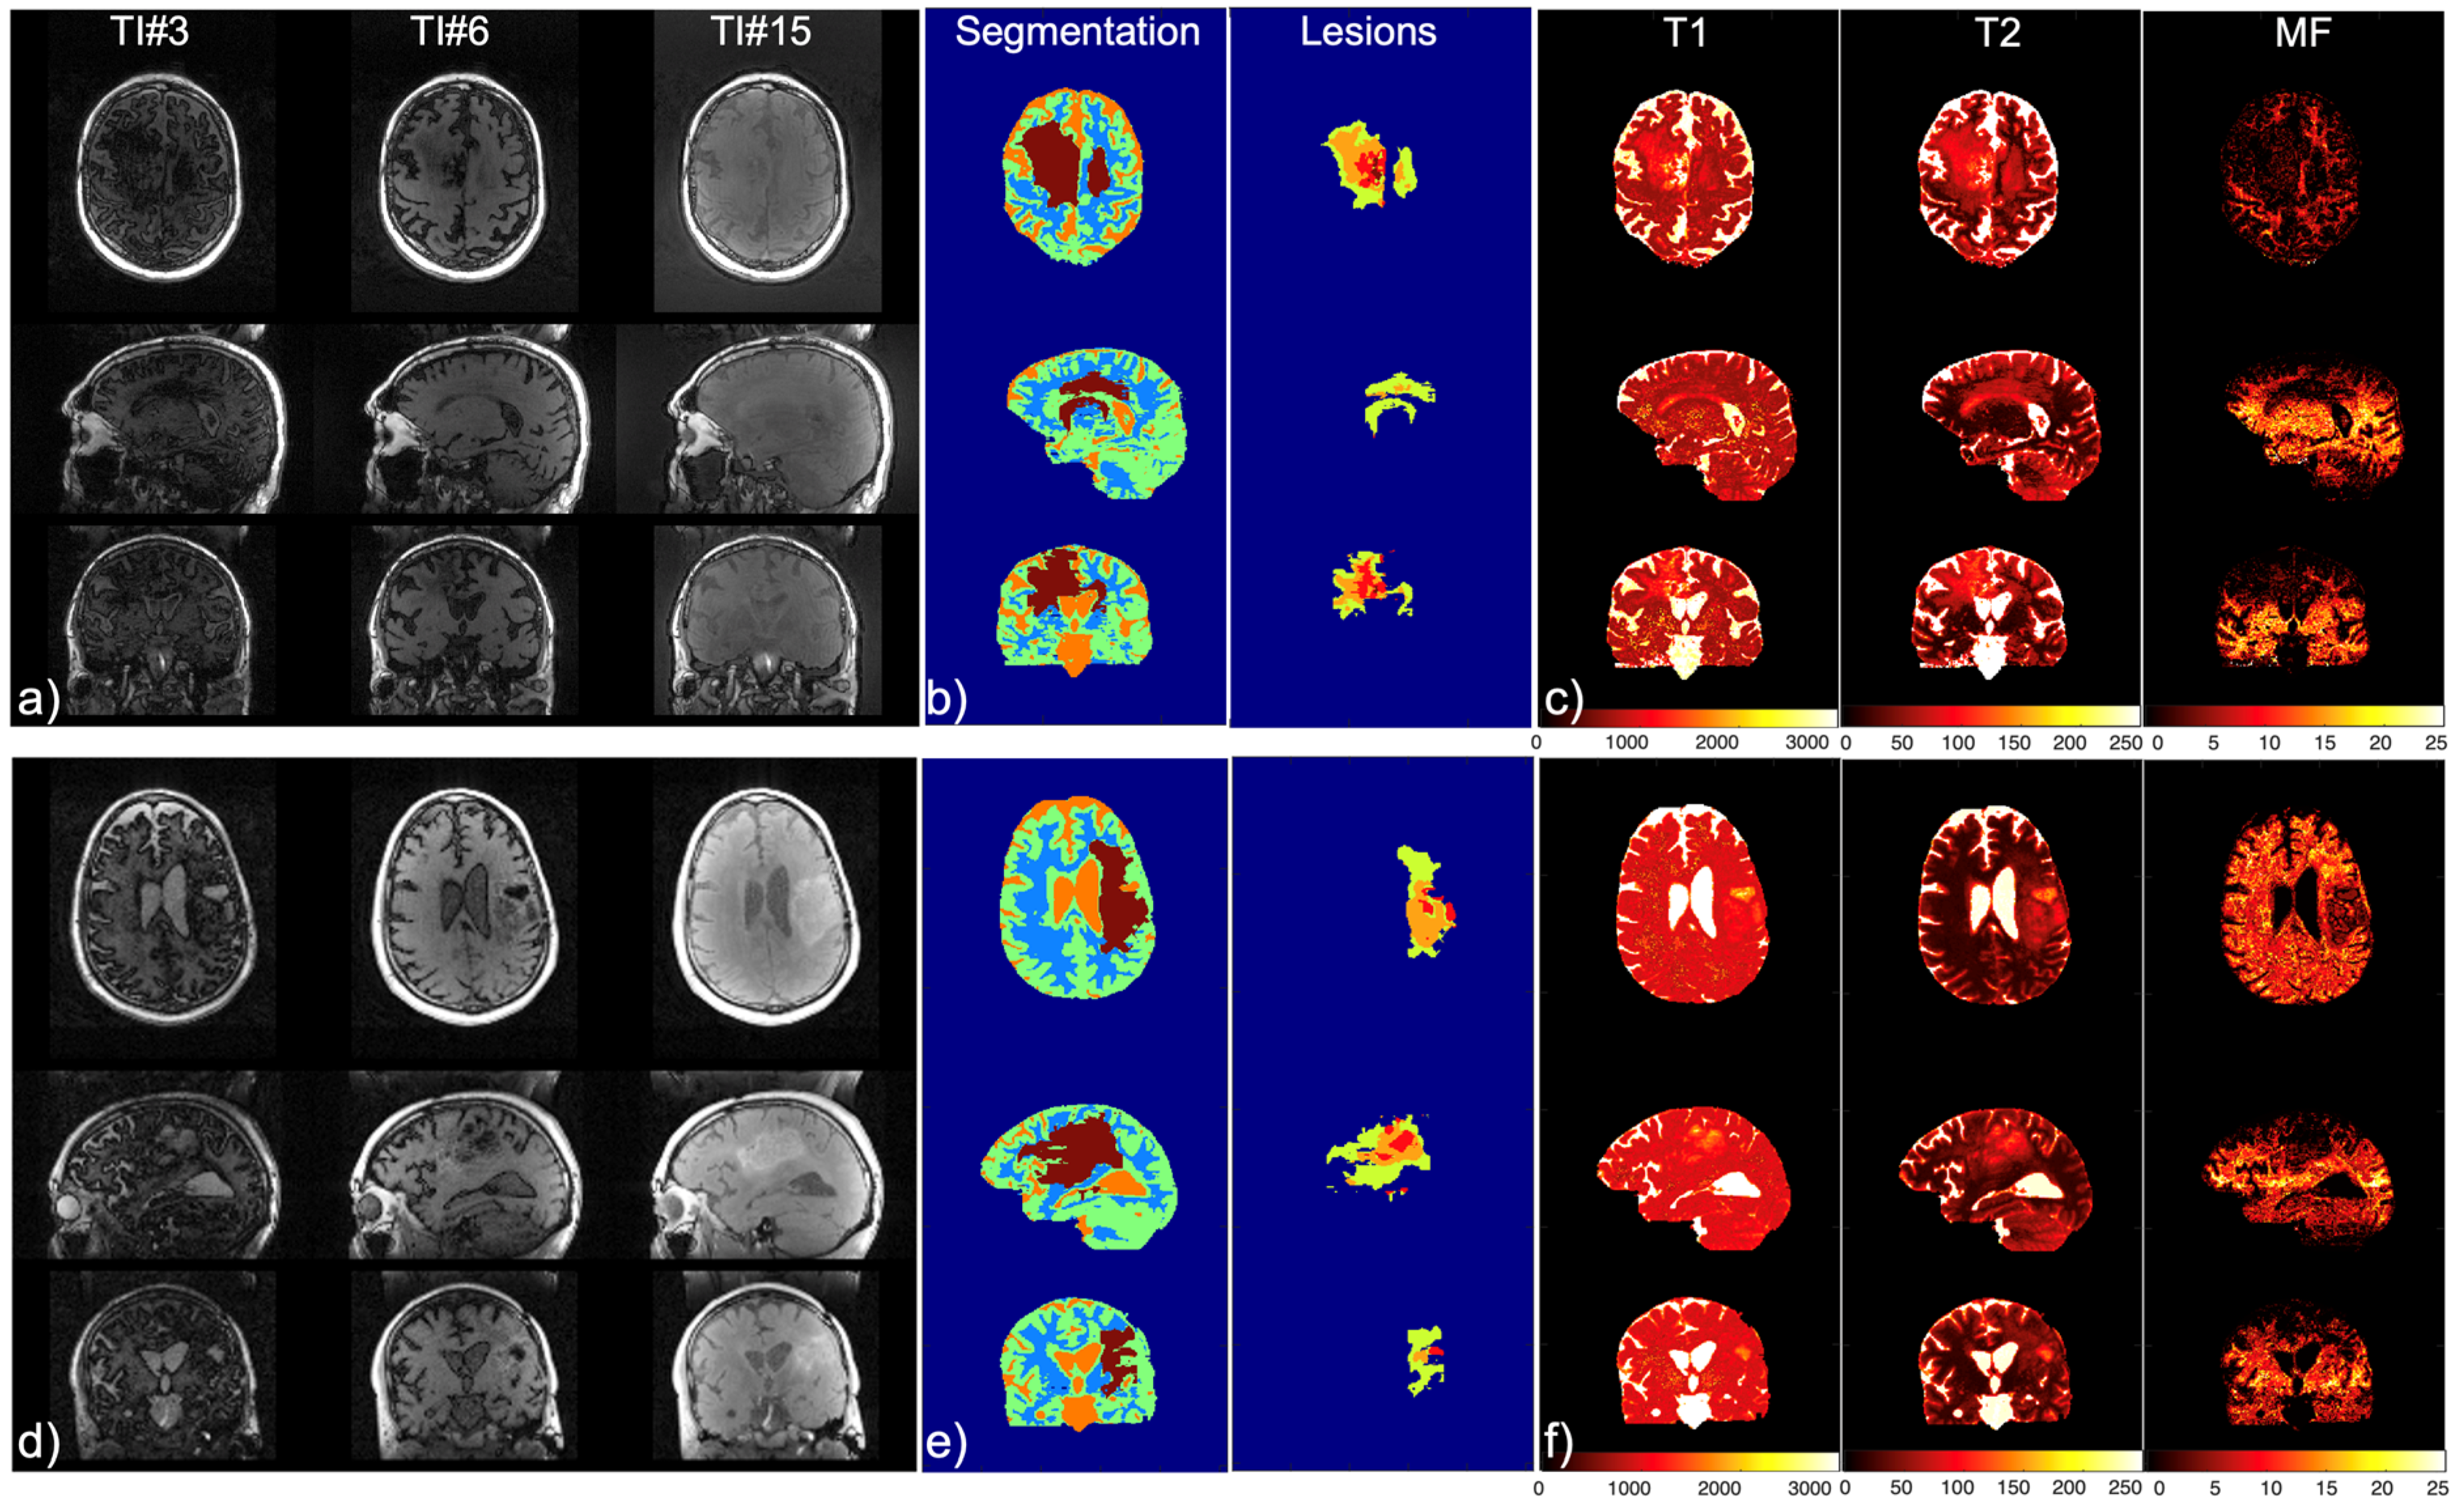

| Mapping | WM | GM | T2L-1 | T2L-2 | CEL | NEC |

|---|---|---|---|---|---|---|

| 2D T1 (ms) | 1186.4 ± 110.5 | 1589.5 ± 331.7 | 1451.5 ± 317 | 1657.9 ± 409.3 | 1947.8 ± 465.6 | 2022.3 ± 459.3 |

| 2D T2 (ms) | 90.4 ± 2.7 | 117.5 ± 12.8 | 114.7 ± 14.2 | 138.2 ± 21.3 | 153.4 ± 47.6 | 152.0 ± 41.1 |

| 3D MWF (%) | 30.4 ± 3.4 | 9.5 ± 3.3 | 12.5 ± 9.3 | 2.3 ± 1.8 | 0.55 ± 0.4 | 0.15 ± 0.0 |

| IIR-bSSFP T1 (ms) | 797.5 ± 88.3 | 670.4 ± 60.2 | 610.9 ± 58.1 | 598.4 ± 77.8 | 958.8 ± 204.9 | 1876.7 ± 608.8 |

| IIR-bSSFP T2 (ms) | 22.0 ± 5.7 | 85.2 ± 8.8 | 62.9 ± 26.5 | 115.4 ± 11.2 | 121.5 ± 10.1 | 157.5 ± 42.0 |

| IIR-bSSFP MF (%) | 14.9 ± 2.5 | 8.7 ± 1.9 | 11.9 ± 3.8 | 5.5 ± 2.6 | 3.6 ± 2.0 | 1.6 ± 0.5 |

| Mapping | CSF | WM | GM | T2L-1 | T2L-2 | CEL | NEC |

|---|---|---|---|---|---|---|---|

| IIR-bSSFP T1 (ms) | 2990.4 ± 277.4 | 848.0 ± 135.5 | 912.4 ± 218.4 | 749.5 ± 217.2 | 883.8 ± 238.8 | 1300.7 ± 303.4 | 2696.6 ± 749.7 |

| IIR-bSSFP T2 (ms) | 218.1 ± 14.9 | 28.5 ± 5.3 | 83.1 ± 20.9 | 62.2 ± 22.4 | 94.1 ± 29.1 | 115.8 ± 19.1 | 190.7 ± 31.9 |

| IIR-bSSFP MF (%) | 1.0 ± 0.4 | 10.0 ± 2.8 | 5.3 ± 1.3 | 7.8 ± 3.4 | 3.4 ± 1.3 | 2.6 ± 1.0 | 2.2 ± 1.2 |